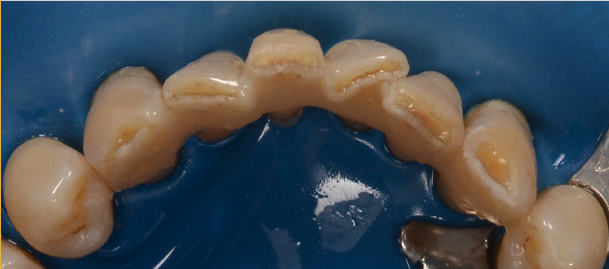

Banda de imobilizare are culoarea aproximativă cu cea a dinților, singurul inconvenient fiind volumul ușor mărit cu care pacientul se obișnuiește în 1-2 zile. (Fig. 5.4.4 și 5.4.5).